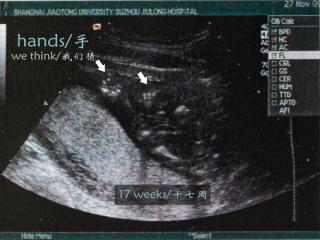

Jak rozwija się nienarodzone dziecko? Powstała animacja, która edukuje i porusza

Organizacja Live Action stworzyła animację ilustrującą rozwój życia dziecka w łonie matki. „Baby Olivia” pokazuje, że życie ludzkie zaczyna się od poczęcia i od tego momentu należy je otoczyć ochroną. „Film należy pokazać każdemu, kto rozważa aborcję” – powiedziała Lila Rose, prezes Live Action.